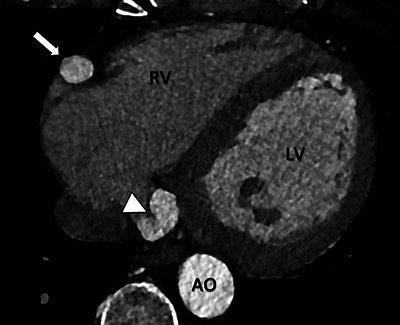

Teaching points: A coronary artery fistula (CAF) is an uncommon anomaly characterized by a diverse clinical spectrum, ranging from asymptomatic cases to severe complications, including heart failure and myocardial infarction.